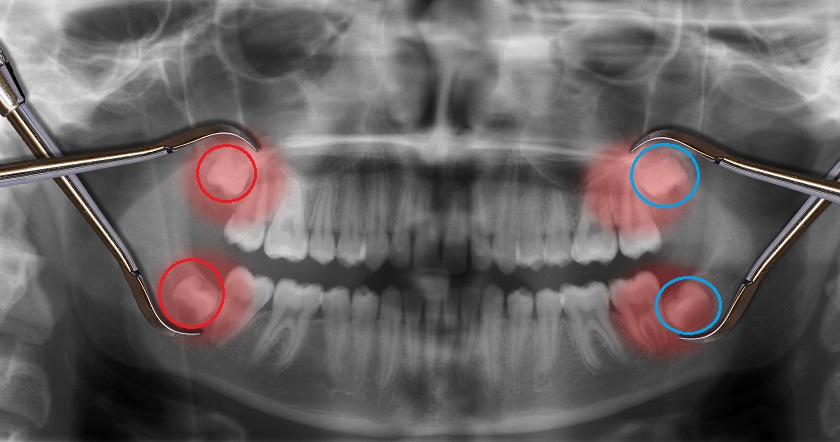

“Nhổ 2 răng khôn cùng lúc có thể thực hiện được không?” thì trong từng trường hợp cụ thể cần có sự thăm khám của Bác sĩ, phân tích và xác định qua hình chụp X-quang, xem xét có nguy hiểm hay ảnh hưởng gì không mới có thể kết luận được.

Để tránh làm tổn thương toàn hàm, Bác sĩ chỉ nhổ 2 răng khôn cùng lúc khi 2 răng nằm ở cùng một bên hàm, nghĩa là hai răng mọc đối diện nhau. Nếu nhổ 2 răng khôn nằm ở 2 bên hàm thì sẽ khiến bệnh nhân gặp khó khăn trong quá trình ăn uống sau khi nhổ răng. Điều này làm ảnh hưởng đến sức khỏe bệnh nhân.